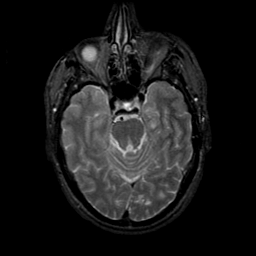

MR Study #9, April 14, 1991 -- Slice #17

[Home][Help][Clinical][Tour 1][Tour 2] Slice 17